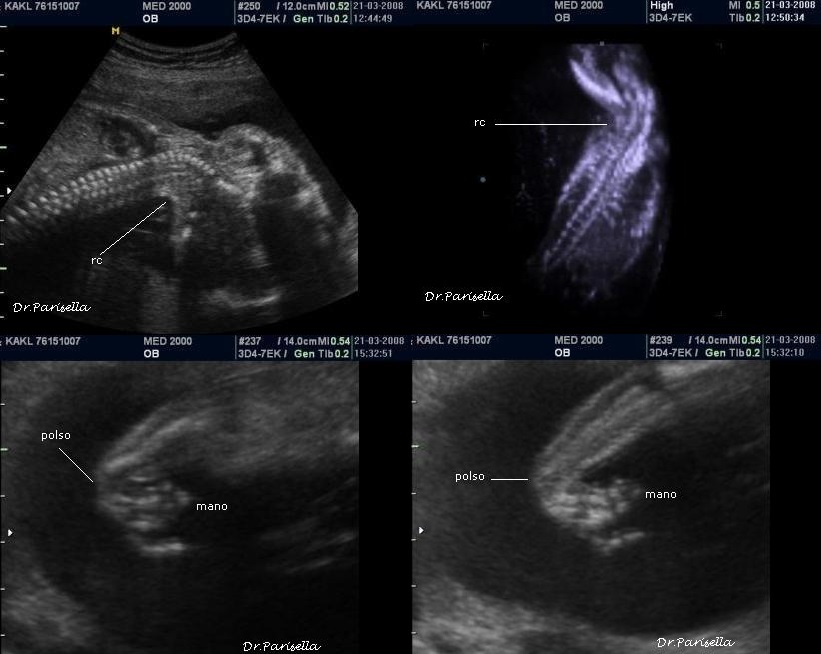

1) assenza di movimenti attivi fetali;

2) artrogriposi caratterizzata principalmente da contratture in flessione;